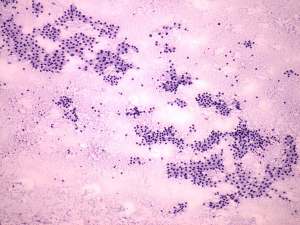

Cytology was performed from the right thyroid. Cytological diagnosis: benign pattern corresponding to hyperthyroidism.TSAb proved to be minimally elevated 2.4 U/mL (normal value below 1.5).